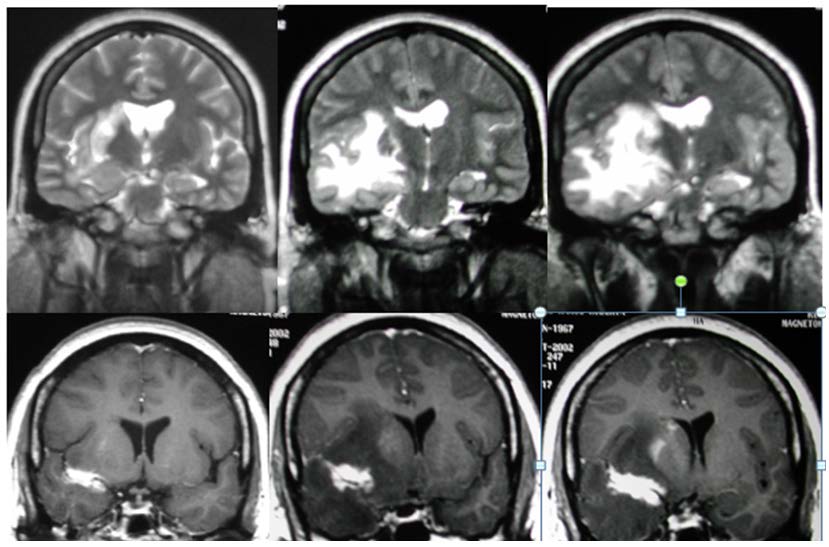

Acompañamos la presente comunicación con imágenes de RM en las que se grafica el «vaso centinela» a nivel frontal derecho (figura 1), fronto-parietal derecho (figura 2) y fronto-temporal derecho (figura 3).

Imágenes de RM sin gadolinio: cortes coronales en T2. RM con gadolinio: cortes coronales en T1 Se observa una formación granulomatosa captadora, fronto-temporal derecha adyacente al valle silviano derecho con gran edema perilesional. También se observa, de modo adyacente y lateral, la forma captadora de un vaso o cola, ya mencionada